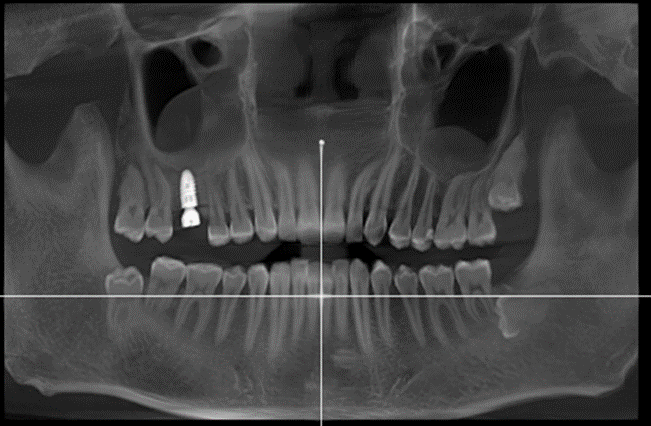

1.拍全景片,查看口腔的具体情况,是否有炎症、牙槽骨吸收等情况

全景片:下图是已经植入种植体装了基台,还没有戴牙冠